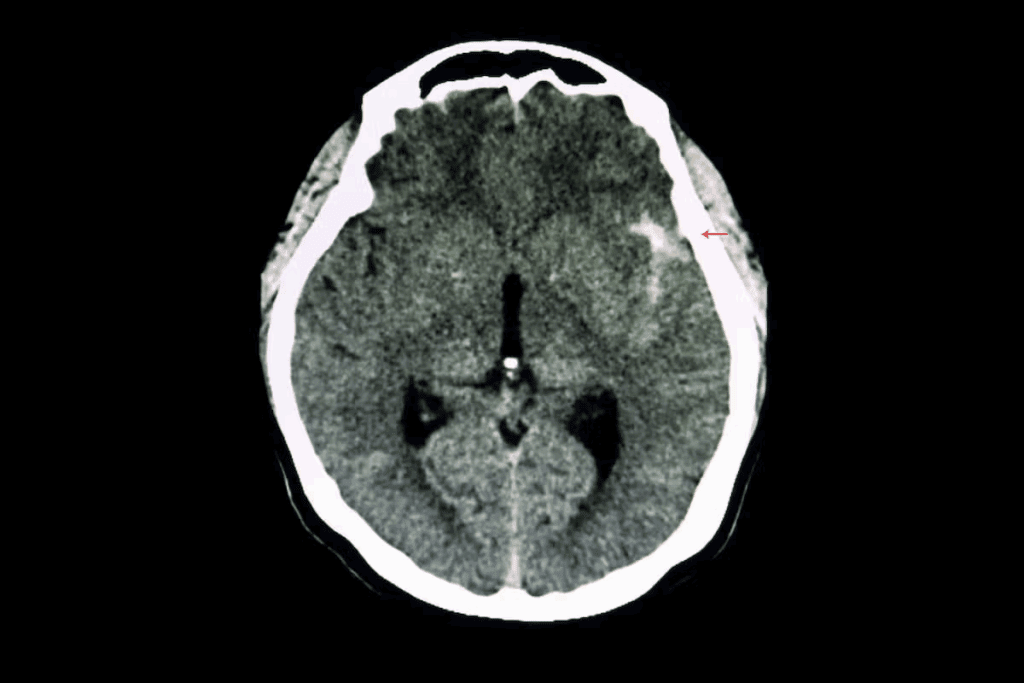

A brain aneurysm is a bulge in a blood vessel in the brain. It happens when the blood vessel wall is weak. Brain aneurysms can rupture, leading to bleeding in the brain, known as a subarachnoid hemorrhage, which is a life-threatening condition requiring immediate medical attention.

If left untreated, brain aneurysms can rupture, leading to severe consequences. The rupture can cause:

- Hemorrhagic stroke

- Brain damage

- Disability

- Death

The importance of timely medical intervention cannot be overstated. Treatments like endovascular coiling can effectively manage aneurysms, preventing rupture and its devastating outcomes.